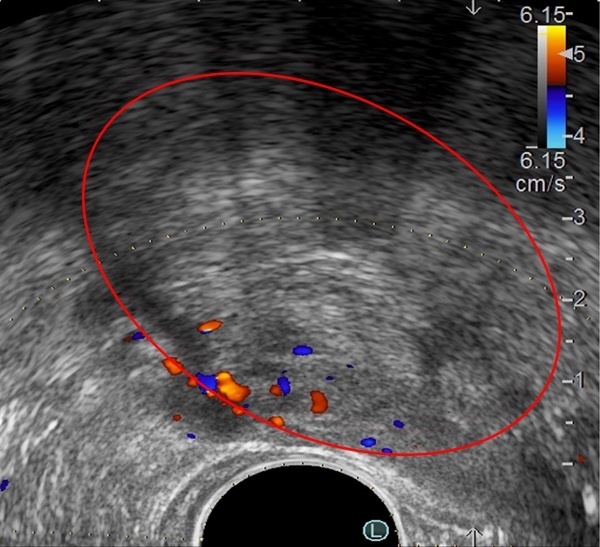

Hình ảnh khối u tuyến tiền liệt qua siêu âm. |

Thăm khám trực tiếp cho ông Hồng Liên là TS.BS Nguyễn Hoàng Đức (Trưởng khoa Tiết niệu - Trung tâm Tiết niệu - Thận học). Qua triệu chứng lâm sàng, bác sĩ siêu âm và sinh thiết tuyến tiền liệt. Kết quả cho thấy ông Liên bị phì đại lành tính tuyến tiền liệt. Tuy nhiên, thể tích của tuyến tiền liệt đến 240 ml, gấp 8 lần mức cho phép ở người lớn tuổi (thường 30-40 ml), lồi vào bên trong bàng quang, bít tắc đường thoát nước tiểu.